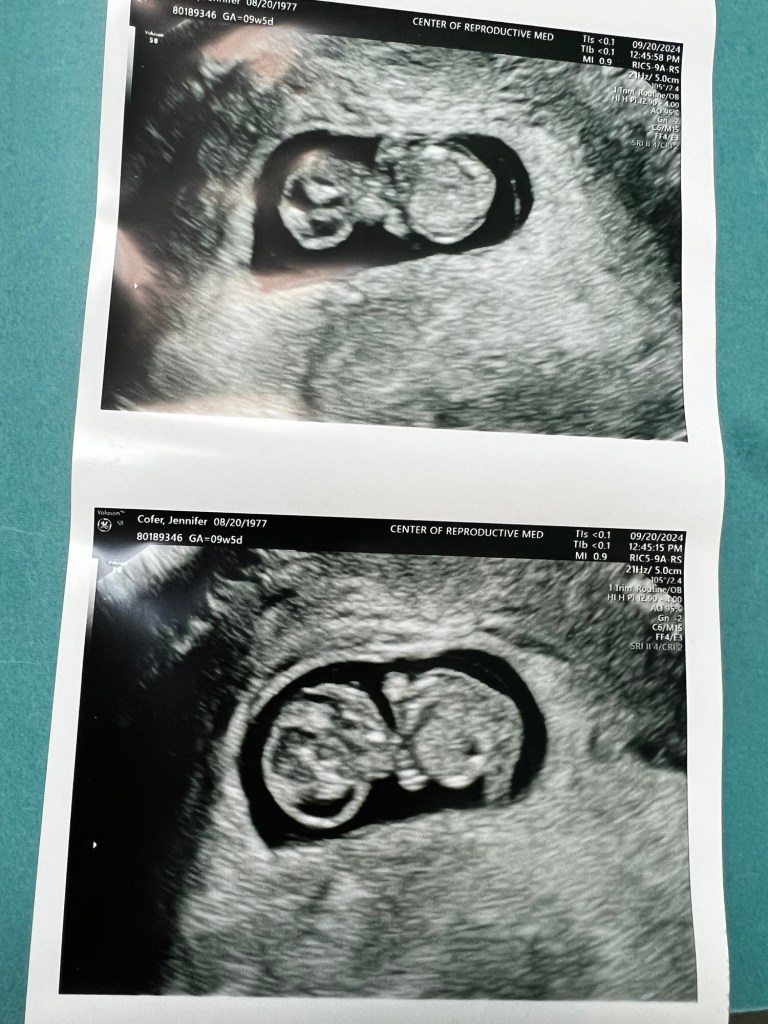

September 5th – I have an ultrasound and bring a friend with me for this 6-week appointment. The one where last year I went by myself and heard the words, there’s no heartbeat or embryo detected. The ultrasound tech finds a gestational sac, and I hear a heartbeat of 153 bpm! My friend and I squeezed hands. By the way, the same friend who drove me and my mom to my D&C the year before. They project the due date of April 25, 2025, and I can’t even think that far ahead.

I went in on September 20th for my final visit and to get checked post travel. This visit was a positive relief. I graduated from my IVF clinic that day. I had another amazing work friend, go with me for this appointment and see my ultrasound of the baby and hear his heartbeat. It was so special and I was elated.

Back to the spotting, after getting worked into my OB, the ultrasound showed a sub-chorionic hematoma in the uterine lining near the gestational sac and it was trying to work itself out or it gets absorbed into the body. This was the reason for spotting old blood. Baby Oliver’s heart rate was 158 bpm at this visit!